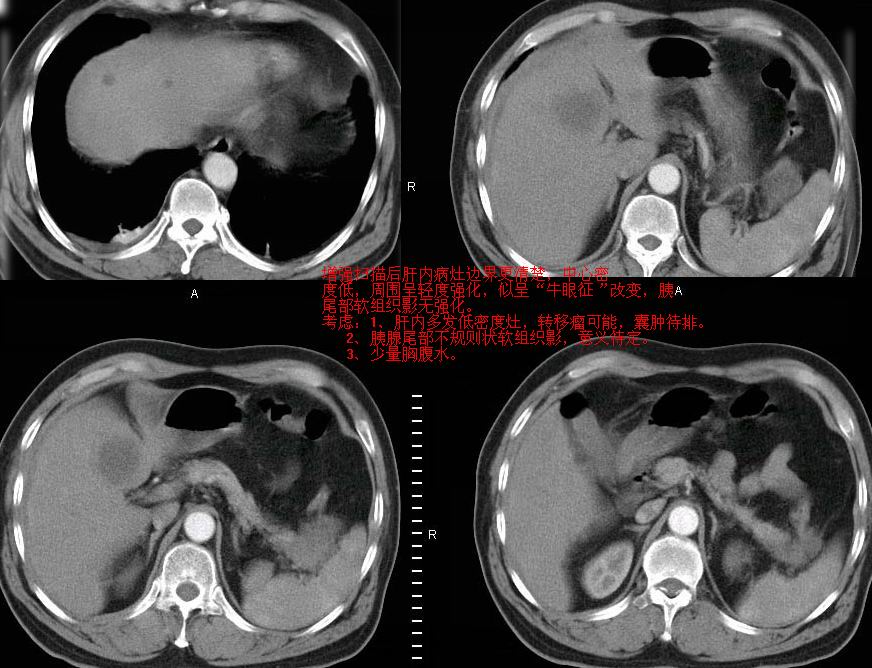

牛眼征,中心坏死无强化,外缘强化,最外缘又见低密度,考虑转移,与脓肿鉴别

1)肝脏多发性转移瘤(不排除胰尾癌转移所致可能)。2)腹水。3)右侧少量胸腔积液。

ct25082 结果:转移瘤

外院mr结果:胰尾恶性占位。

肝多发低密度灶;轻度强化,较水密度高,考虑转移,不排除肝脓肿